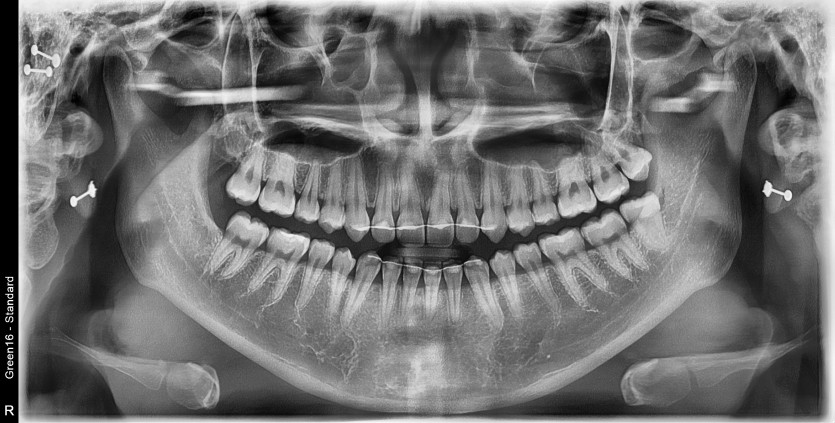

#28,38 사랑니 발치

구강 외과 전문의가 당일 발치했습니다.